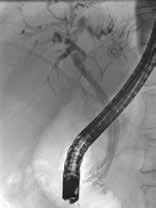

Standard behandling av benigne strikturer har vært ERCP med gjentatte dilatasjoner og innleggelse av multiple plaststenter i gallegang over en periode på ett år (Fig 5). De senere år har bruk av selvekspanderende metallstent i 6-12 mnd. blitt mer vanlig dersom forholdene teknisk ligger til rette for dette. Det er imidlertid risiko for residiv av striktur på grunn av progresjon av grunntilstanden så gjentatt endoskopisk behandling kan bli nødvendig.